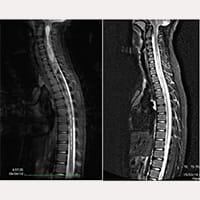

Between October 1993 and July 2017, more than 1000 patients affected by the Neuro-Cranio-Vertebral Syndrome and/or the Filum Disease with Arnold Chiari I, Syringomyelia and Scoliosis (in different diagnostic combinations) have been treated according to the guidelines of the FILUM SYSTEM®.